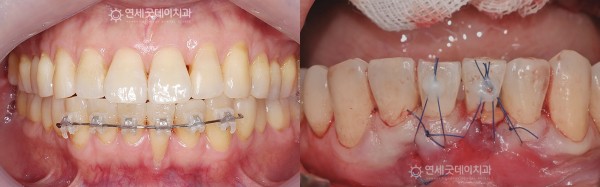

● 담당과 : 교정과 + 치주과

● 치료요약 : 아랫니부분교정과 핀홀을 동반하여 치주교정 진행

환자분은 아랫니부분교정을

약 8~10개월 가량 선행한 뒤

핀홀 잇몸수술을 하는 치료계획으로 진행되었습니다.

약 5개월 간의 아랫니부분교정만으로도

내려갔던 잇몸이 점차 차오르는 양상을 보였습니다.

교정을 마친 후에는

입천장에서 채취한 잇몸조직과

콜라겐 차폐막, 엠도게인을 함께 적용하여

잇몸이식수술을 진행했습니다.

약 9개월 간의 아랫니부분교정과 핀홀수술로

건강하고 심미적으로 복구된 모습입니다.

치료한 부위가 어디인지 구분하기 어려울 정도로

자연스럽고 두툼한 잇몸이 형성되었습니다.